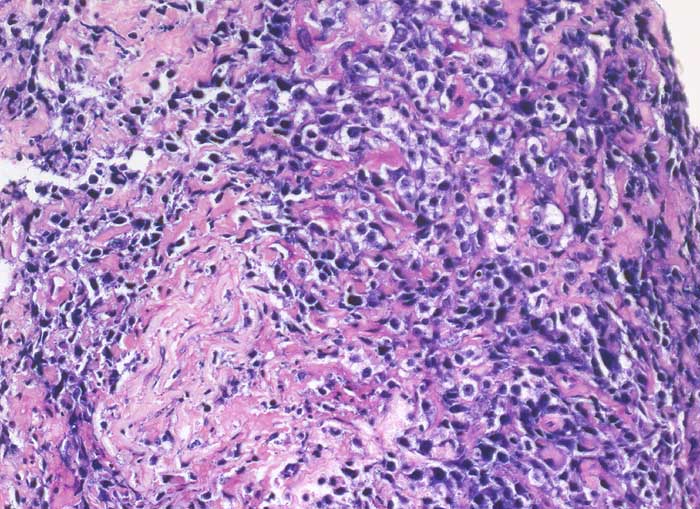

Nierenhilusweichteile: diffuse Infiltrate atypischer lymphoider Zellelemente mit klarem Zytoplasmasaum.

Immunphänotypisch sind die Tumorzellen positiv für den Pan-B-Zell-Marker CD20 und fokal positiv für CD10. Daneben reaktive CD3 und CD5 positive T-Zellen. Negativ sind Antikörper gegen Zytokeratine sowie gegen Nierenzell-assoziierte Antigene. Die Prolfierationsrate ist hoch, stellenweise über 80%.